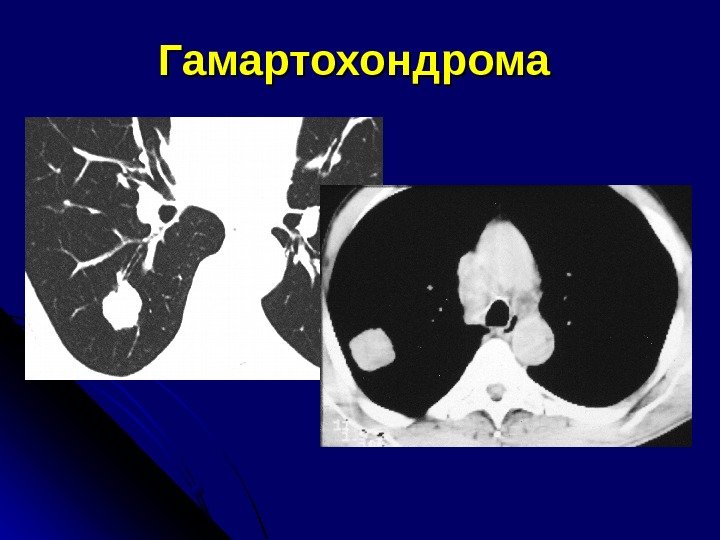

Р и КТ-признаки гамартохондром Любого размера В любом отделе Контуры – ровные, волнистые, четкие Наличие участков повышенной плотности в центре (хрящевые включения) – патогномоничный признак

Гамартохондрома

КТ-признаки гамартом Форма – округлая или бобовидная Контуры – четкие Плотные включения (костные обызвествления) – 30% — денс. плотность > 70 НЕ Жир Патогномоничный признак – сочетание крупных обызвествлений и жировых включений